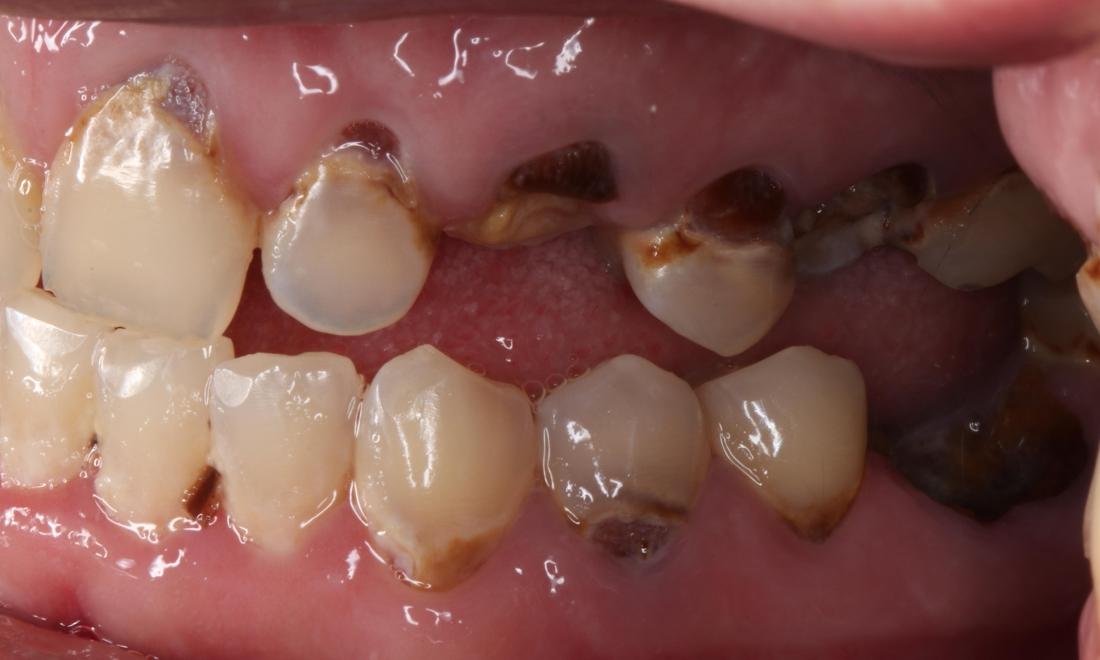

After a long journey to sobriety, this patient was ready to get his mouth healthy along with the rest of his body.  He was ready to smile with his kids again and jumpstart his new career.

Close up of mouth from a side view before a complete smile makeover, nashville tn Close up of mouth from a side view after a complete smile makeover, nashville tn